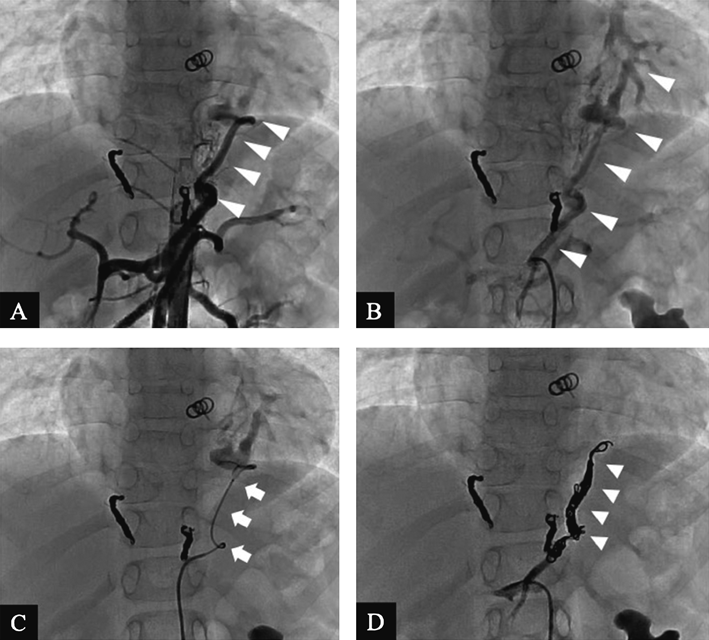

症例1:7歳,男児,体肺側副動脈

造影検査にて対象血管を同定し(Fig. 1-A),対象血管を選択造影する(Fig. 1-B).血流量多く,屈曲あり4 Fr造影カテーテルが途中までしか進まないため,より太いガイディングシースなどが要求されるAVP IIはもちろん,4 Frカテーテルから使用可能なAVP4,Azur 35コイル(テルモ,東京,日本)やoff-labelではあるが使用する機会のあるFlipper PDAコイル(Cook, Bloomington, IN, USA)などの0.035インチコイルも最初のコイルとしては不適と考えた.対象血管は動脈で留置するコイルにかかる圧も高く,血流によって遠位部にコイルが移動する可能性があり,最初に留置するコイルとしてはアンカリング力を重要視した.4 Fr造影カテーテルがより末梢まで進んでいれば,アンカリング力の高いFlipper PDAコイルを最初のコイルとして使用することを検討していたが,4 Frカテーテルの到達位置から断念せざるを得ず,マイクロカテーテル経由で留置を行うコイルの中ではアンカリング力の高いPODコイル4 mm–30 cm(Penumbra, Alameda, CA, USA)を最初のコイルとして使用する計画とした.PODコイル使用のためマイクロカテーテルはハイフロータイプを選択した.コイル留置の際には塞栓を開始する部位と終了する部位の選定は重要で,留置したコイルの移動の危険性が少なくなると考えられる狭窄や屈曲があり,かつ遺残短絡に対して追加治療が可能となるスペースも残しておく必要がある.末梢がより細くなる対象血管の場合は遠位部へのコイルの移動は考慮する必要がないためその点においては安心して手技が可能だが,末梢に移動してしまうと重要血管の塞栓につながる形態の対象血管では最初に留置したコイルがその場所に留まってくれることが最重要となるため解剖学的な状況およびコイルの特性を考慮しながらコイルを選択することになる.マイクロカテーテルをコイル留置開始部まで進め選択造影を行った(Fig. 1-C).PODコイル挿入後にアンラベルしない程度の弱いテンションをかけてコイルが移動しないことを確認後に離脱した.PODコイルの特徴としてアンカリング力に優れているが,これだけでは血流量の多いこの対象血管の塞栓はすぐには期待できないため,追加コイルとしてハイドロゲルを有し高い塞栓力をもつAzur 18とAzur CX 18コイル(テルモ,東京,日本)を選択した.Azur 18とAzur CX 18に対応するマイクロカテーテルはセレクティブタイプとハイフロータイプのいずれでも可能であるため,そのままハイフロータイプのままで留置したが,単独での使用時には我々は操作性を重視してセレクティブタイプを使用することが多い.我々は経験からセレクティブタイプを用いて留置を試みたほうが前述したコイルを送り出す力が伝わりやすく,ランディングゾーンを短くすることができる印象を持っている.Azur 18とAzur CX 18を留置後も遺残短絡をわずかに認め,4 Frカテーテルからの追加治療を考えた.選択肢としてはAVP4やFlipper PDAコイルやAzur 35コイルなどの0.035インチコイルなどがあるが,下行大動脈までのランディングゾーンを考慮してAzur 35コイルを留置し,完全閉塞を確認した(Fig. 1-D).使用した合計6本のコイルを使用順にTable 1に列記する.

Fig. 1 Aortopulmonary collaterals. Angiograms show A) Aortopulmonary collateral (arrowhead) arising from the descending aorta and B) Selective angiography via 4 Fr catheter shows aortopulmonary collateral (arrowhead). C) The microcatheter (arrow) was advanced through a 4 Fr catheter to the initial coil placement point. Selective angiography via microcatheter shows aortopulmonary collateral. D) After coil (arrowhead) placement, no residual flow is present.

Table 1 Coil used in case 1

CoilDiameter-LengthNo of coil

POD4 mm–30 cm1

Azur CX184 mm–13 cm3

Azur 184 mm–5 cm1

Azur 354 mm–10 cm1